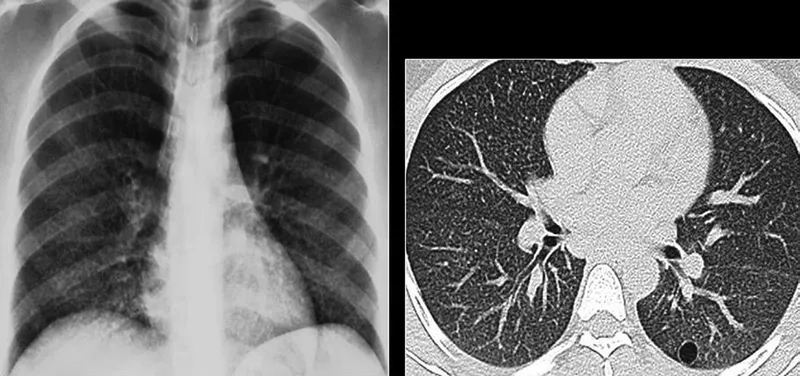

• A diagnosis of PCP often involves a chest x-ray, which typically shows diffuse bilateral infiltrates, a key indicator for healthcare providers.

Image of the disease Pneumocystis Pneumonia